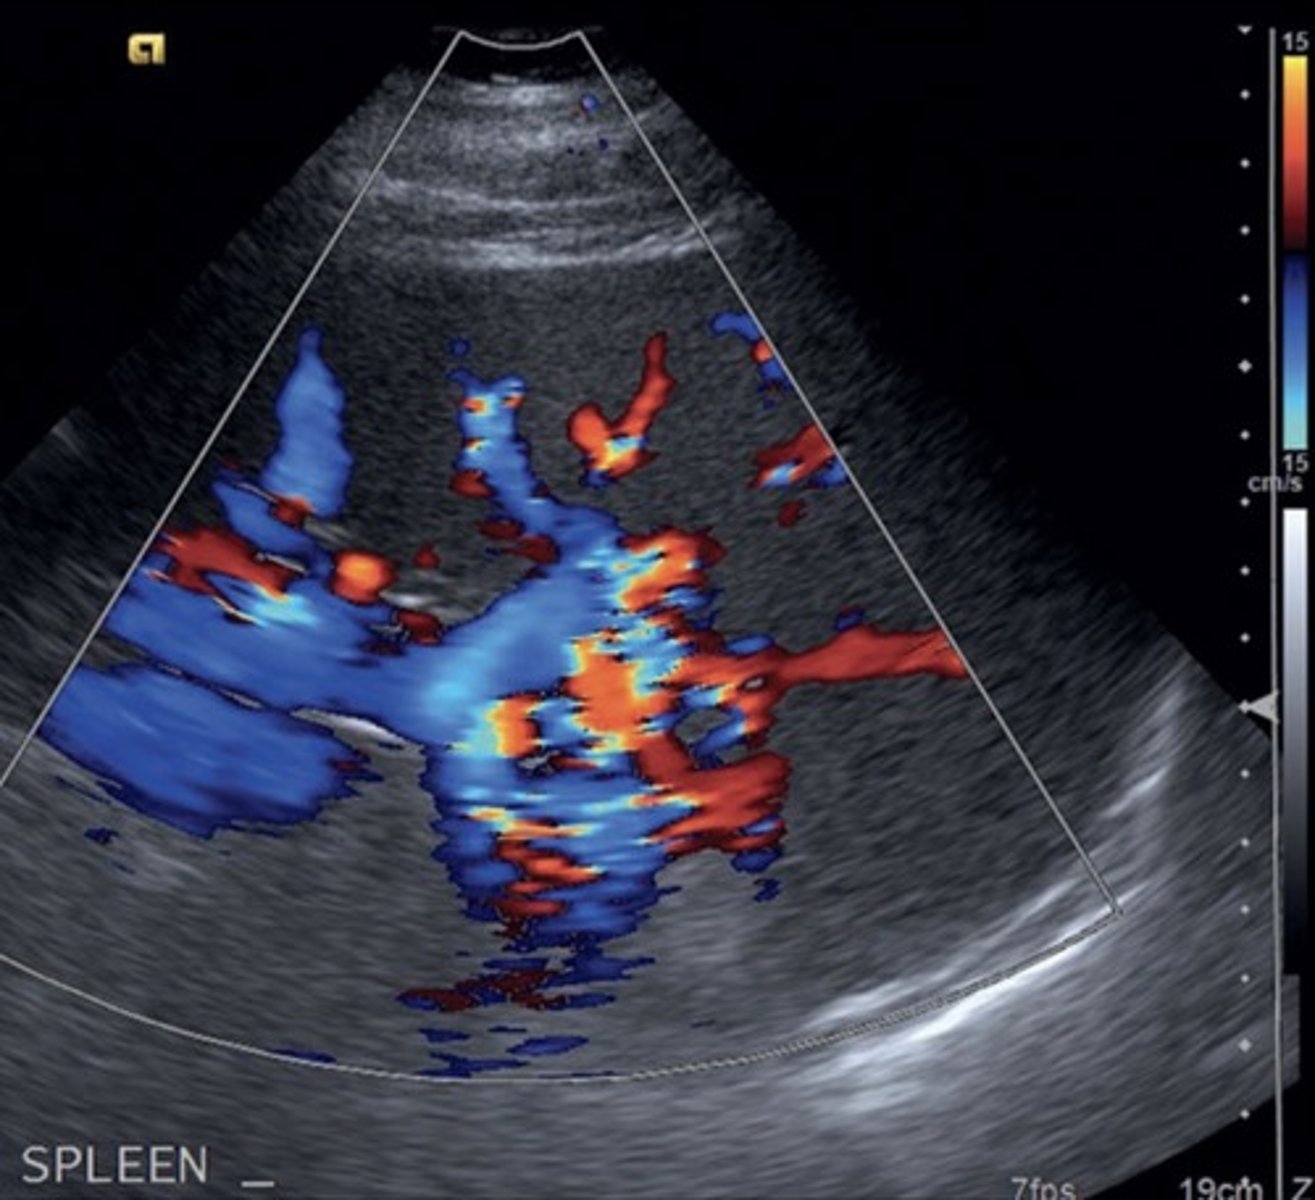

Splenorenal Shunt

Prominent veins at splenic hilum

Hepatofugal flow in splenic vein

Gastroesophageal Veins/Esophageal Varices

Originate from gastroesophageal junction posterior to left liver lobe

Due to hepatofugal flow in coronary vein shunt

High risk of rupture